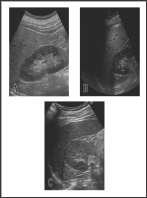

Figure 1: The change of the findings of abdominal ultrasonography during the course.

a. Hepato-renal echo contrast that is typically observed

in fatty liver 4 months before admission.

b. The similar finding was observed at the time of

admission.

c. Hepato-renal echo contrast was almost disappeared

on 108 days after discharge from the hospital.

A 71 years-old man who had worked as a landscaper until 5 years ago was admitted to our hospital for the elevation of CK levels (2782 IU/mL, normal range: 0-180) and deterioration of both gastrocnemius muscle pains. His body height was 174 cm and body weight was 80.5 kg (BMI 26.6 kg/m2), thus, he was thought to be obesity. His body temperature was normal (96.4 °F), and no abnormalities were also shown in other vital signs. He had no history of allergy, edema in lower limbs, goiter, hoarseness, and skin roughness. He had been treated hypercholesterolemia by statins for 11 years (pravastatin, atorvastatin, and rosuvastatin in this order) and add-on ezetimibe had been administered since 6 years before. Since 11 years before, his alanine aminotransferase (ALT) had been mildly elevated (approximately 50 IU/L), and ultrasonog-raphy had kept showing fatty liver such as (Figure 1A). He had also been treated diabetes mellitus (DM) by glimepiride, alogliptin, and voglibose since 6 years before. Although self-reported dietary intake was not changed, his body weight was gradually increased (57 kg [body mass index (BMI) 18.8 kg/m2] in 3 years ago, 62 kg [BMI 20.5 kg/m2] in a year ago, and 64 kg [BMI 21.1 kg/m2] in 5 months ago). Therefore, nutrition intervention was performed, but it was not effective. In addition, he had sometimes felt mild both gastroc- nemius muscle pains without specific factors such as exercise since 10 years before, and his CK levels had been slightly elevated (ap- proximately 400 IU/L).

At the time of admission, his laboratory data showed a significant elevation of CK levels, but CK-MB and myoglobin levels were within normal range. In addition, aspartate aminotransferase (AST), ALT, lactate dehydrogenase, y-glutamyltransferase, total cholesterol, low-density lipoprotein cholesterol (LDL), triglyceride, and hemoglobin A1c (HbAlc) levels were also elevated (Table 1). Physical examination showed no abnormality including goiter. Abdominal ultrasonography showed fatty liver same as before (Figure 1B). Although aggressive excise was not likely to be performed and he seemed not to spend outside so long hours just before hospitalization, myopathy due to dehydration based on high outdoor air temperature (the lowest and highest temperature in Gunma prefecture from one day before his hospitalization to the hospitalization day were about 77 oF and 95 oF, respectively.) was suspected.

Therefore, we started to perform rehydration therapy (1000 to 1500 ml/day). In addition, rosuvastatin and ezetimibe were discontinued because those might have caused myopathy. As a result, CK levels tended to be decreased, but it had been remained around 1000 IU/L from days 5 to 10 of admission. AST and ALT levels were also increased. On day 12 of admission, we suspected the elevation of CK levels due to hypothyroidism. Then, we found that thyroid stimulating hormone (TSH) levels were elevated (234 μU/ mL) and free T3 and free T4 levels were below the detection limit. Besides, anti-thyroglobulin antibody and anti-thyroid peroxydase antibody were also positive. Thyroid ultrasonography showed the hypoechogenicity and heterogeneity of thyroid gland. Based on these results, he was diagnosed as chronic thyroiditis (Hashimoto's disease). Liver biopsy performed for the evaluation about the cause of increased transaminase levels showed 30% steatosis, balloon-like change of hepatocytes, pericellular fibrosis, and portal fibrosis. Thus, he was diagnosed as NASH with grade 1 and stage 2 by Brunt's classification (Figures 2A & 2B) [6]. As thyroid hormone replacement therapy, levothyroxine was started at 25 μg/day and was gradually increased. As a result, thyroid function, CK levels, ALT levels, and muscle pain were improved, and he was discharged on day 40 of admission. On day 73 after discharge from the hospital, ALT levels were elevated to 115 IU/L and TSH levels remained at 71 μIU/mL although CK levels were improved. Therefore, levothyroxine was increased to 75 ng/day. Later, ALT and TSH levels were improved. On day 109 after discharge from the hospital, his body weight and BMI were improved to 71.9 kg and 23.7 kg/m2, respectively. LDL cholesterol and triglyceride levels were fluctuated after the discontinuation of rosuvastatin and ezetimibe but gradually decreased with increase of levothyroxine. Triglyceride levels reached to the normal range while LDL cholesterol levels almost reached to same levels as before the admission without antihyperlipidemic agents. HbA1c levels were gradually decreased after admission, and finally reached to the lower levels compared to those before admission without increase of oral hypoglycemic agents. Second liver biopsy showed the improvement of steatosis (Figures 2C & 2D), and abdominal ultrasonography also showed the improvement of hepato-renal echo contrast (Figure 1C). The clinical course is shown in (Figure 3).